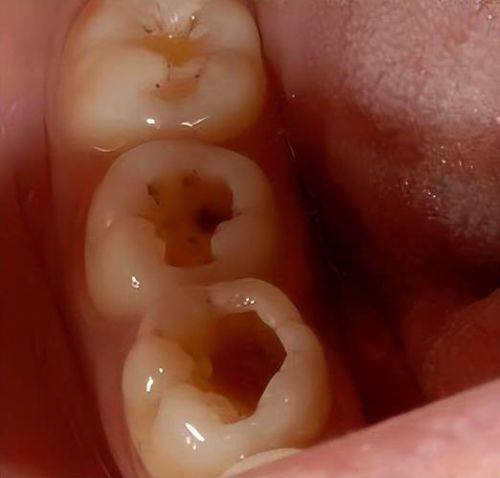

牙齿本身问题:先天的“小缺陷”

除了生活习惯,牙齿本身的状况也会影响龋齿的发生。个体之间存在差异,部分人群牙齿矿化程度较高,牙齿表面的硬度较大,较易抵御细菌的侵袭;而部分人群牙齿存在较深的窝沟,这些窝沟就像是细菌的“藏身之处”,细菌容易藏匿其中,增加了龋齿发生的几率。

对于牙齿窝沟较深的人来说,必要时可进行窝沟封闭。窝沟封闭是一种预防龋齿的有效方法,它可以将窝沟填平,防止细菌和食物残渣进入,从而降低龋齿的发生风险。